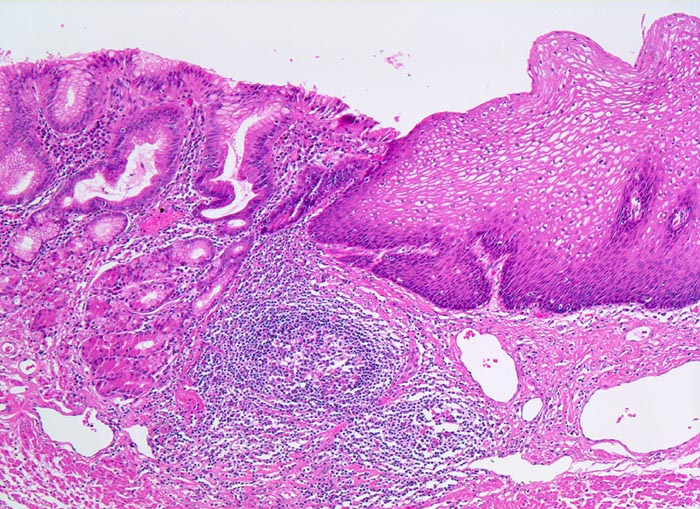

• Distales Ösophagusteilstück.

• Von oben nach unten: Magenschleimhaut vom Fundustyp mit spezialisierten Magendrüsen, Ösophagusschleimhaut (nicht verhornendes Plattenepithel), Schleimhaut vom Kardiatyp (villoglanduläre Oberfläche, Zylinderzellen) mit herdförmig intestinaler Metaplasie (Becherzellen und Paneth'sche Körnerzellen mit rotem granulärem Zytoplasma) vereinbar mit Barrettmukosa.

• Mässiggradige chronische (Plasmazellen), geringgradig aktive (neutrophile Granulozyten) Entzündung der Magenschleimhaut.

• Keine Epitheldysplasie (intraepitheliale Neoplasie) im Bereich der Barrettmetaplasie.